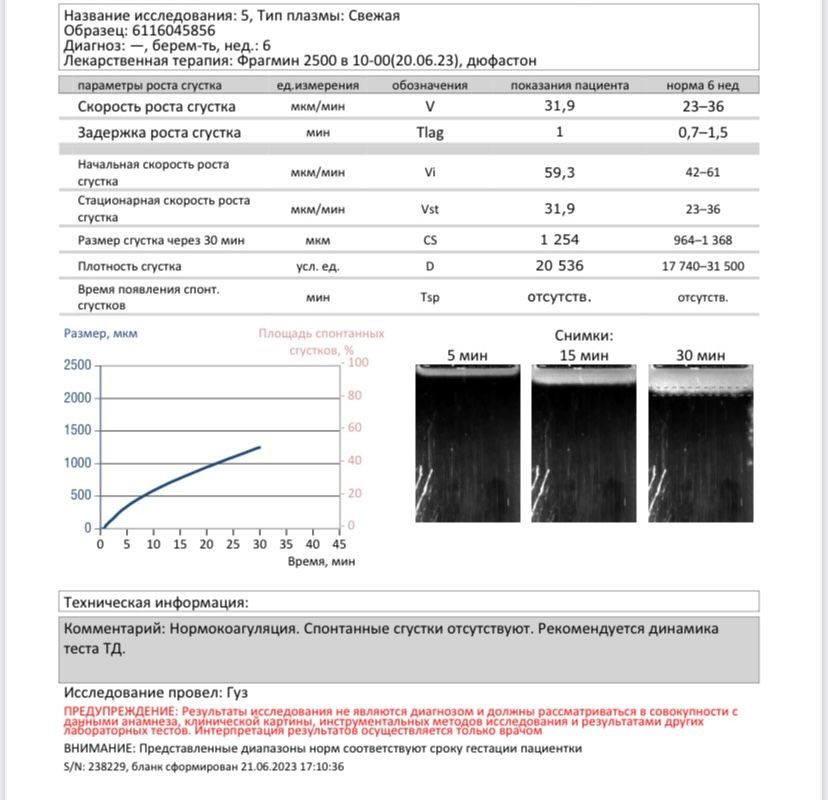

Девушки , добрый вечер! У меня тромбофилия , мутация Лейдена. Колю фрагмин. 6 нед беременности. Сдала тромбодинамику , ддимер, фибринолиз. Подскажите , кто разбирается , все ли нормально ? К гематологу через несколько дней , а я уж конечно , сейчас все хочу разузнать 😅

Polka, нет...абсолютно все значения по середине рефференса практически. И как вообще тромбодинамика может влиять на появление выделений если вы и так на Фраксипарине?! Может она имела ввиду правильность дозы...тромбодинамика для этого и существует чтобы подобрать правильную дозу. Можно переборщить тогда реально есть риск кровотечения, но у вас норма. Сейчас отправлю девочке с опытом по больше у нее тоже тромбофилия и сейчас она на 24 недели уже может я что не вижу в вашем анализе

Викки , спасибо за ответ ! Может , из за того что фибринолиз понижен. Написано норма 5-12 мин, а у меня 4 мин. мне ещё гематолог говорила , что при использовании фрагмин может быть такое , что выделения кровянистые из половых путей начнутся. Но тогда нужно будет транексам принимать и ей звонить. А так , тут только фибринолиз не в пределах нормы